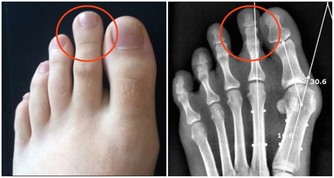

婆婆和先生懷疑的眼光,讓她幾乎崩潰。醫生仔細詢問,她才回憶起自己結婚前,曾在路邊小攤上打過耳洞。“很可能就是那次埋下禍根。”